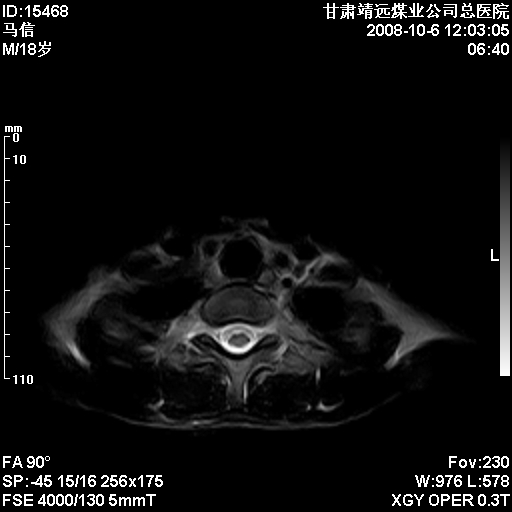

患者18岁,学生,在玩耍中受伤来检查,患者喜欢打篮球。颈椎内异常信号影,我们考虑占位,但是不像占位,又考虑硬膜囊的增厚,大家关建看颈椎椎管内的那个异常占位信号

腰椎的改变是不是正常发育的改变,还是打篮球的长期慢性损伤。

考虑 c3-4 c4-5 c5-6椎间盘突出,l3-4 l4-5 l5-s1椎间盘变性

颈椎建议做增强扫描;腰椎诸椎终板骨骺炎。

脑脊液流动伪影?

后纵韧带增厚,颈2/3、3/4、4/5、5/6椎间盘变性、突出;椎体有旋转,提示椎小关节有问题;腰椎间盘变性,许莫氏结节。

是正常的脑脊液波动伪影

脑脊液流动伪影

你说的占位是伪影。在我们医院1.5t和3.0t的mr上是经常看见的。